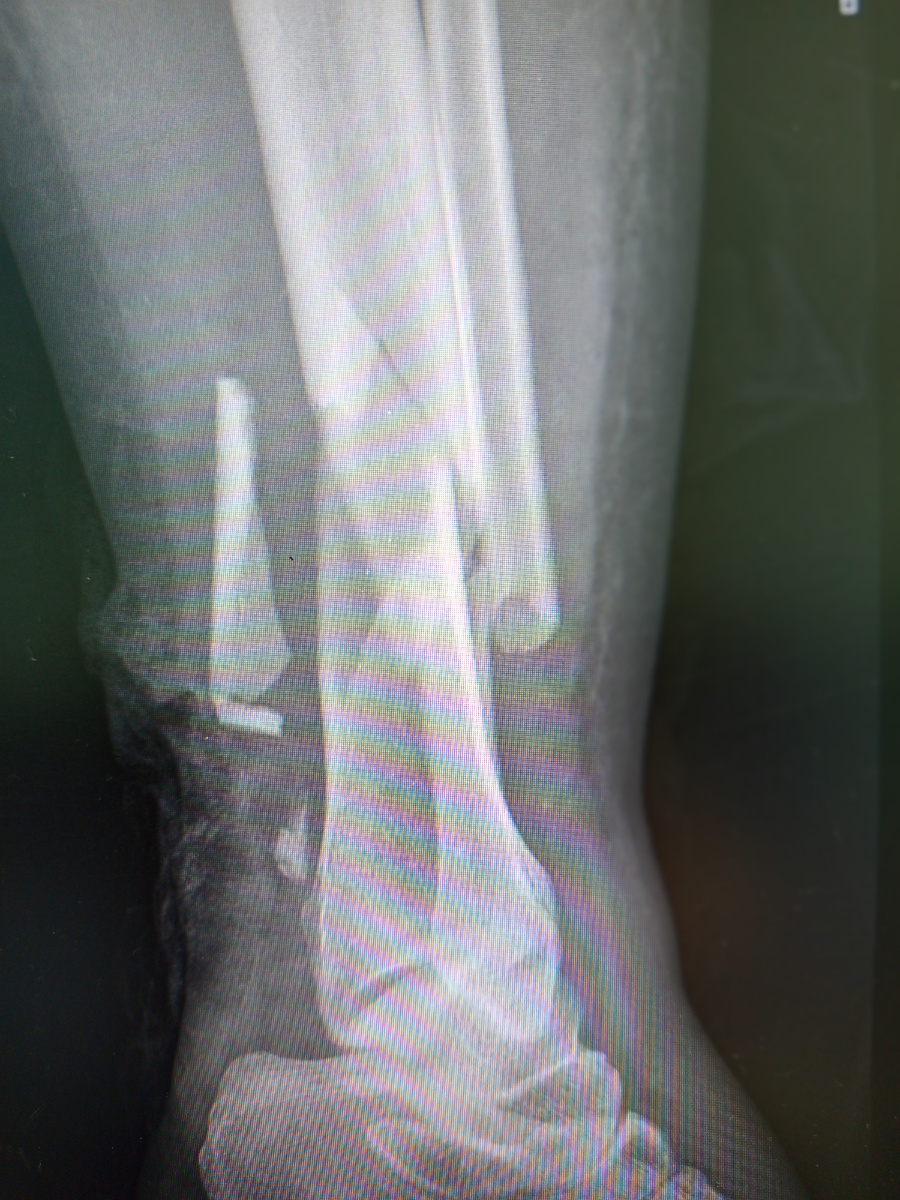

Больше всего не повезло пациентке с красивыми именем Анника.

Плачущая женщина так и сказала , что не помнит, где получила травму, потому что была пьяная.

Открытый перелом голени, с как попало накрученным пропитанным бинтом.

Под непрерывный плач женщины , кое- как сняли две проекции.

–Что там? Я ходить буду?Гипс надо ?– всхлипывая , спрашивает она.

Ну, думаю ,гипс тут мало чем поможет.Как так упала? Останется тайной, ибо пациентка не помнит.